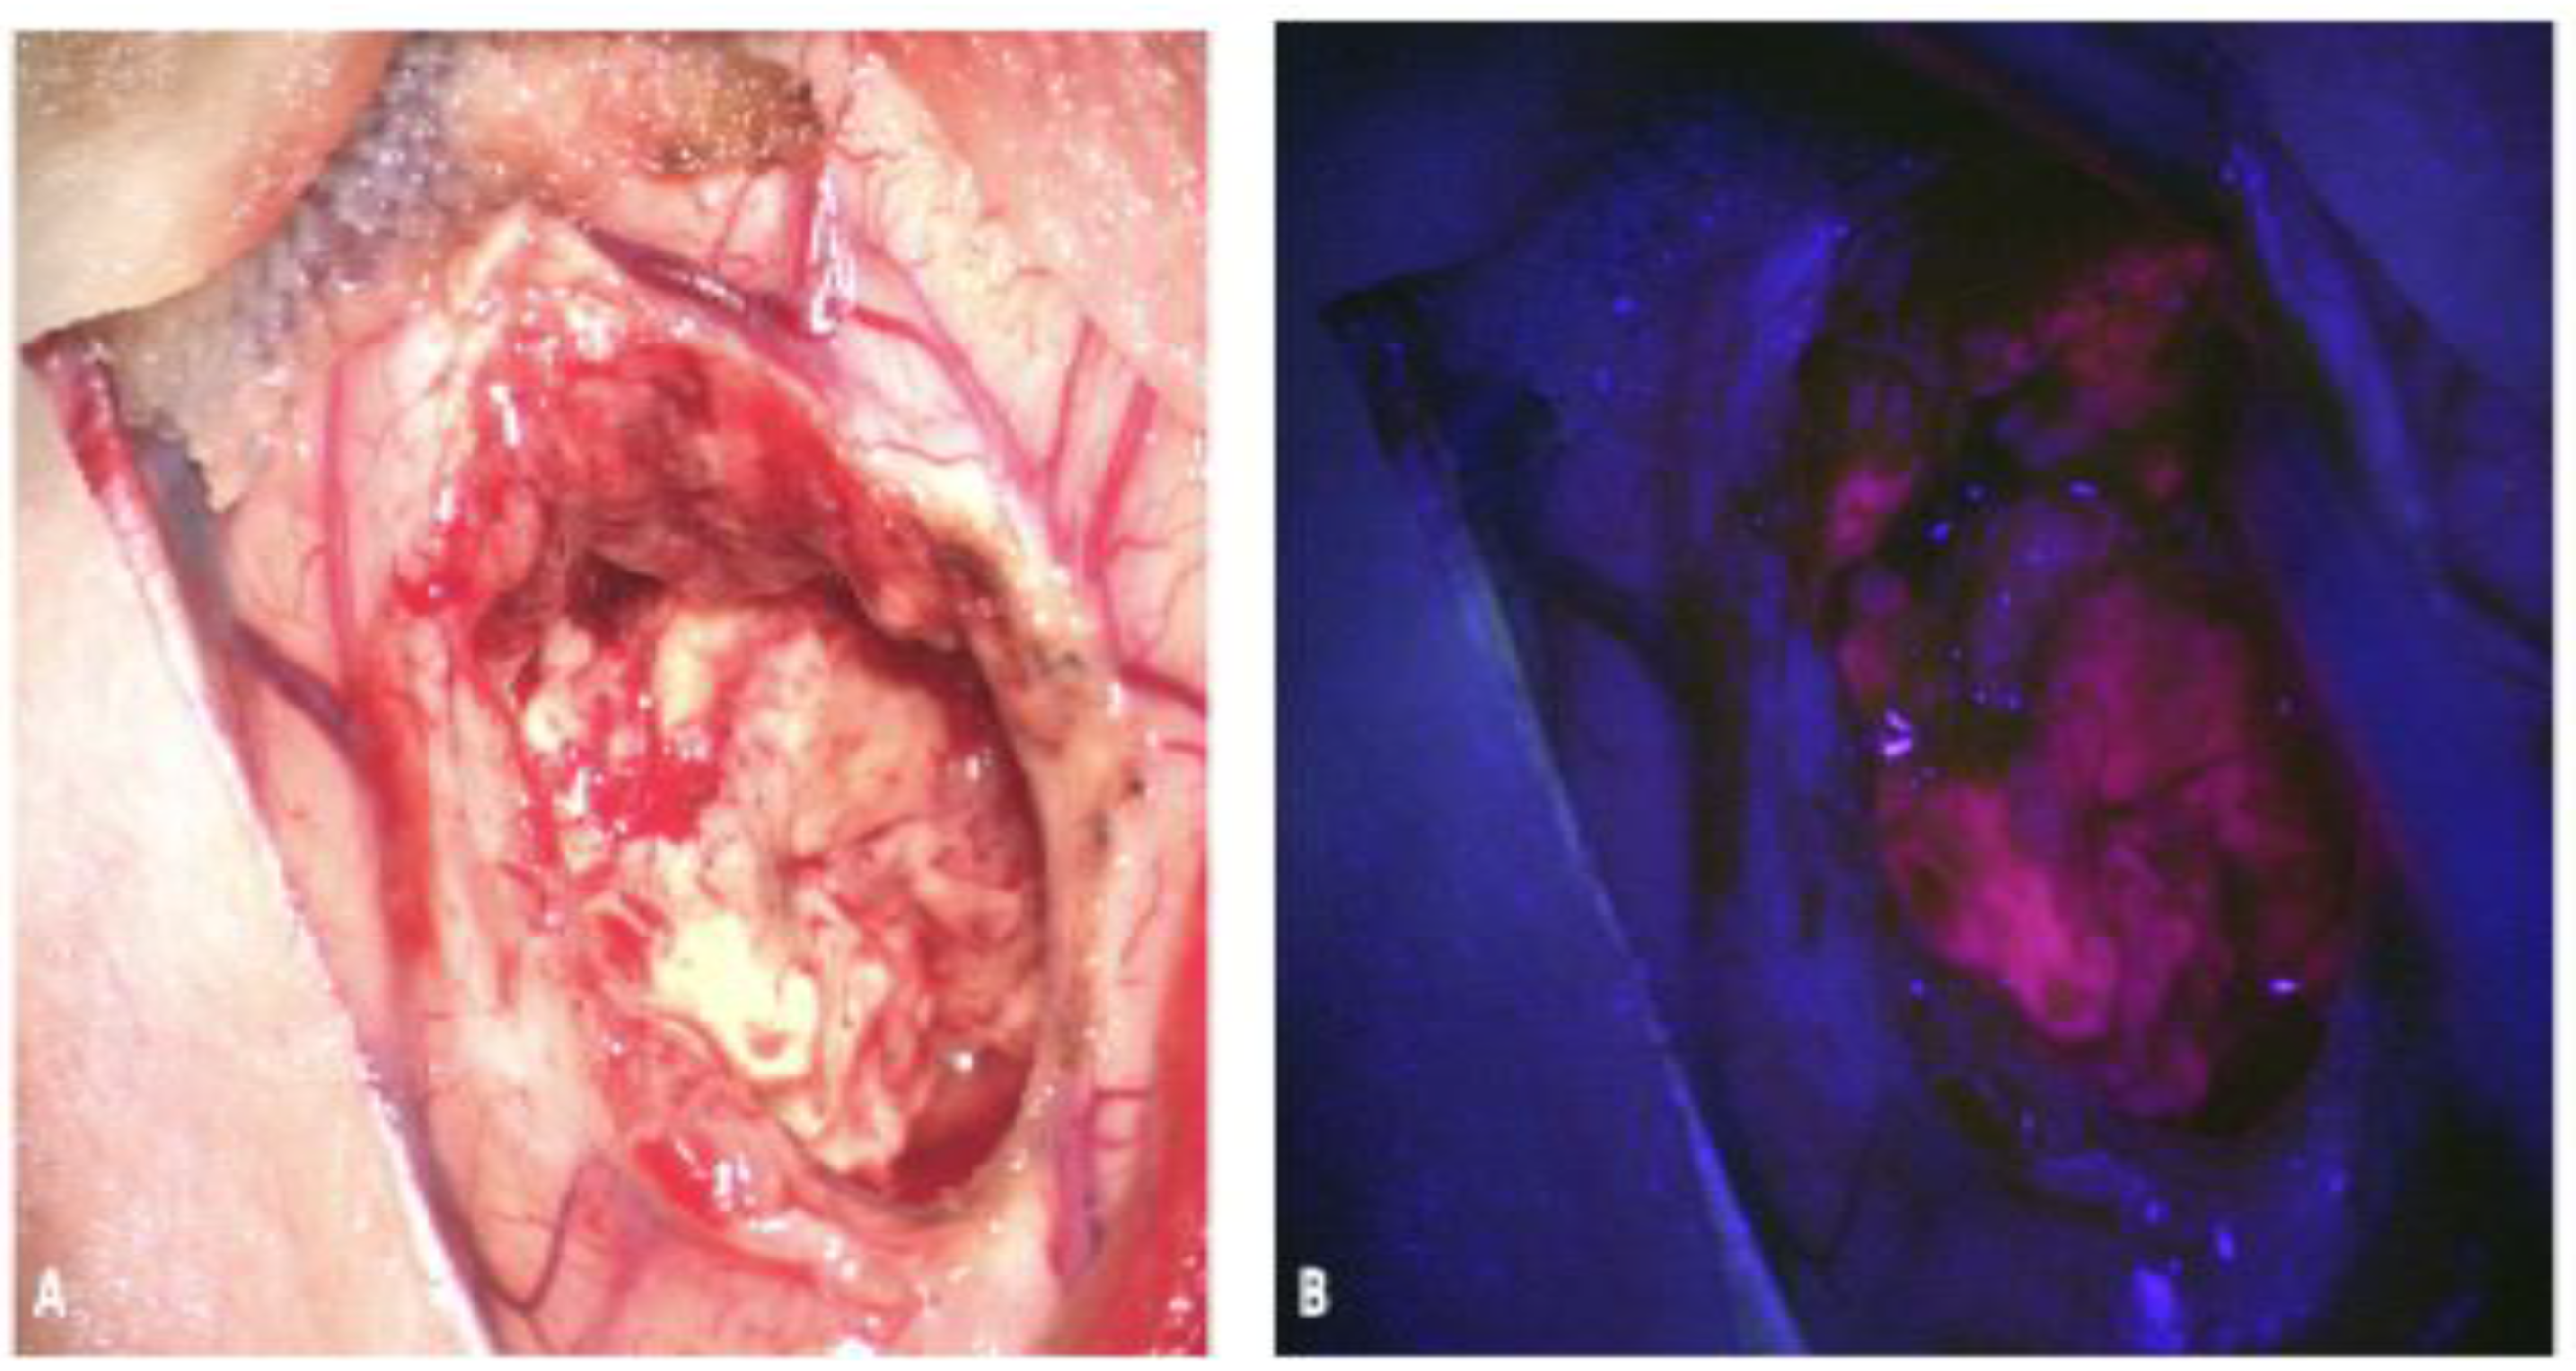

2.2. Fluorescein

2.2.1. Fluorescein: Background and Mechanism of Action

2.2.2. Fluorescein: Evidence for Use

2.2.3. Fluorescein: Limitations